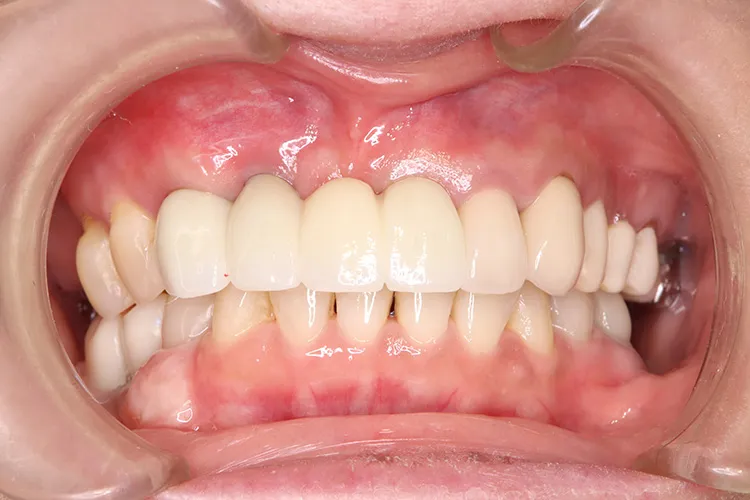

治療前

治療後

レントゲン画像

治療内容

ボーンアンカードブリッジの下顎症例です。同じようにインプラント6本で上部構造を支えることができます。